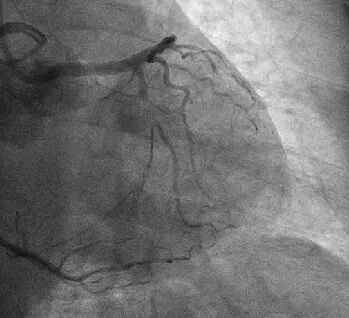

为明确回旋支闭塞病变具体情况,应用逆向造影技术,成功显影回旋支闭塞段(下图↓)。